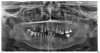

Bier Опубликовано 29 октября, 2012 Поделиться Опубликовано 29 октября, 2012 у вас более-менее сохранные 3 зуба на н.ч. слева. Но есть одно но - их внекостная часть уже больше, чем внутрикостная. Они будут испытывать повышенную нагрузку, расшатываться и терять кость. Если вы гипермотивированы на сохранение этих 3х зубов - должны быть готовы к дополнительным операциям по костной пластике для установки имплантатов (если планируется ставить имплантаты сейчас)Если же имплантаты ставить не будете, а съемным протез, то зубы оставляются + еще тогда можно оставить крайний зуб слева внизу.Но протез их раскачает за 2-3 года. Ссылка на комментарий